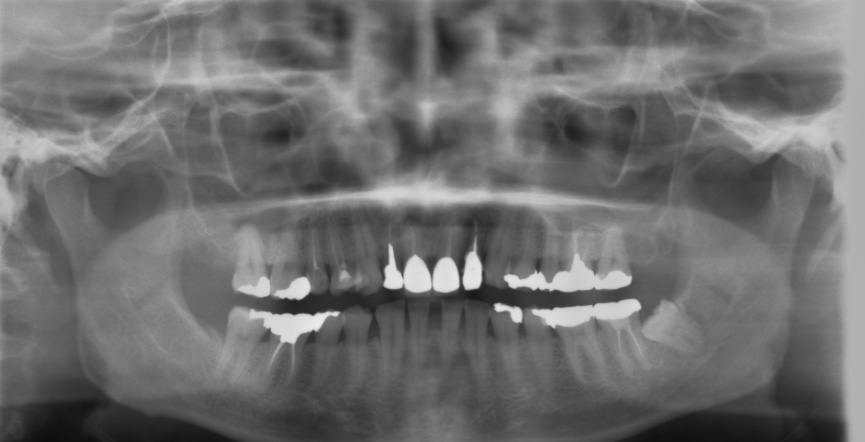

受傷時パノラマレントゲン(2018年5月17日)

初診日 : 2018年5月17日

治療計画 :

・右上3.1番 歯牙破折… インプラントブリッジ

・左上2番 歯牙破折…インプラントブリッジ

・左上1番 脱落…インプラントブリッジ

・右下1番 脱落…ブリッジ